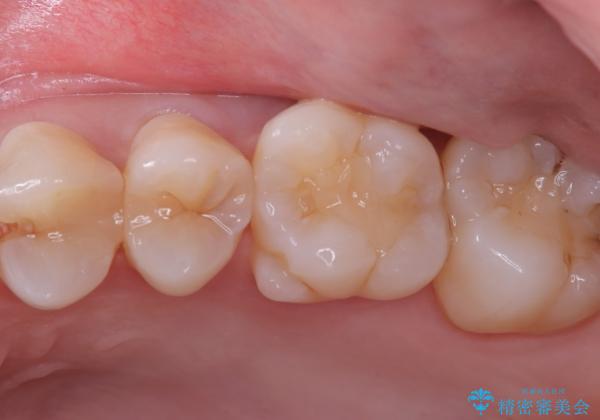

審美性、適合性の良いセラミックインレーでのやり替えとなりました。

インレー接着操作時はラバーダム防湿を行っています。